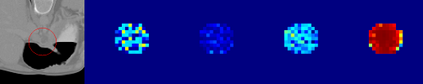

Evaluating lesion progression and treatment response via longitudinal lesion tracking plays a critical role in clinical practice. Automated approaches for this task are motivated by prohibitive labor costs and time consumption when lesion matching is done manually. Previous methods typically lack the integration of local and global information. In this work, we propose a transformer-based approach, termed Transformer Lesion Tracker (TLT). Specifically, we design a Cross Attention-based Transformer (CAT) to capture and combine both global and local information to enhance feature extraction. We also develop a Registration-based Anatomical Attention Module (RAAM) to introduce anatomical information to CAT so that it can focus on useful feature knowledge. A Sparse Selection Strategy (SSS) is presented for selecting features and reducing memory footprint in Transformer training. In addition, we use a global regression to further improve model performance. We conduct experiments on a public dataset to show the superiority of our method and find that our model performance has improved the average Euclidean center error by at least 14.3% (6mm vs. 7mm) compared with the state-of-the-art (SOTA). Code is available at https://github.com/TangWen920812/TLT.